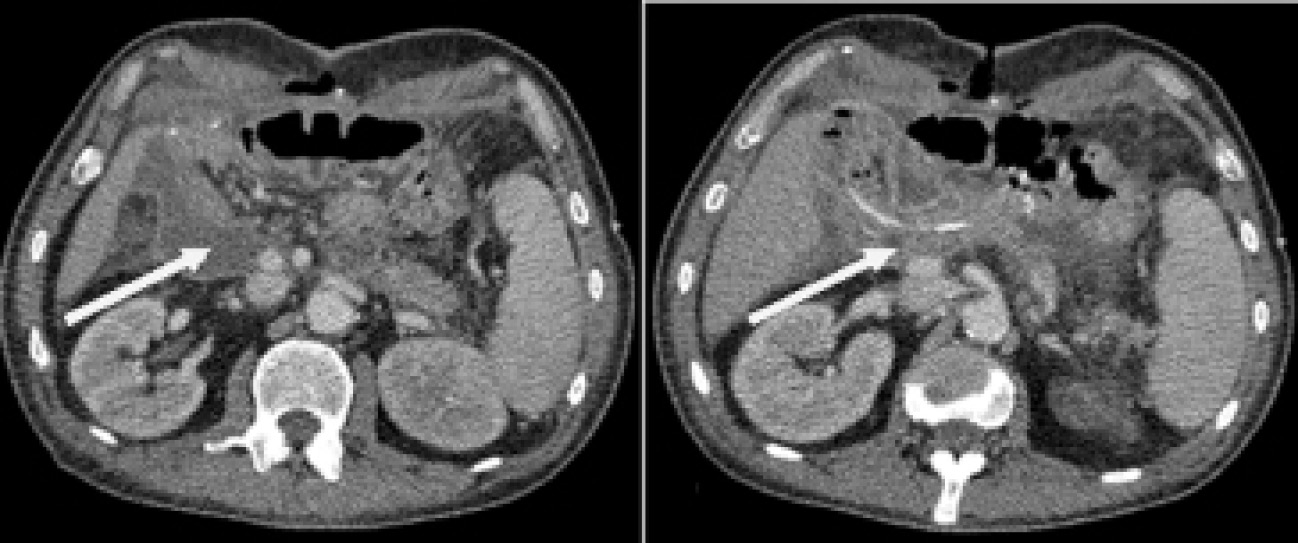

На фоне проводимых мероприятий сохранялись признаки системной воспалительной реакции. По данным компьютерного и ультрасонографического контроля отметили увеличение свободной жидкости в области ПЕА (рис. 7).

Рис. 7. Компьютерная томограмма. А) Свободная жидкость в области ПЕА; Б) Дренирование зоны ПЕА

Учитывая наличие недренирумых отграниченных жидкостных скоплений, выполнено пункционное дренирование под ультрасонографическим контролем на 23-е сут после ГПДР (рис. 8).

Рис. 8. Ультрасонограмма. Отграниченное жидкостное скопление в области ПЕА